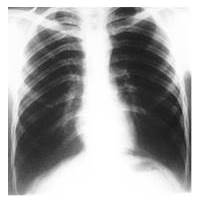

Radiografía simple de tórax póstero anterior y lateral, con imagen radiopaca de apariencia redondeada, de unos 5 cm de diámetro aproximadamente, localizada a nivel del décimo (10o) arco costal posterior izquierdo (Figura 1).